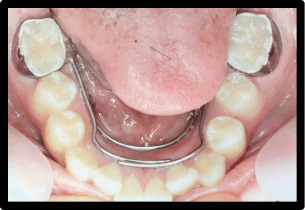

症例2:叢生の矯正治療

BEFORE

AFTER

症例概要

年代・性別

10歳代 女性

主訴

デコボコした歯並びを治したい

治療内容

ブラケット(ワイヤー)を用いた矯正治療

治療期間

4ヶ月

治療のリスク

定期検診、セルフケアを怠ると虫歯になる可能性があります

治療費用

440,000円(税込)